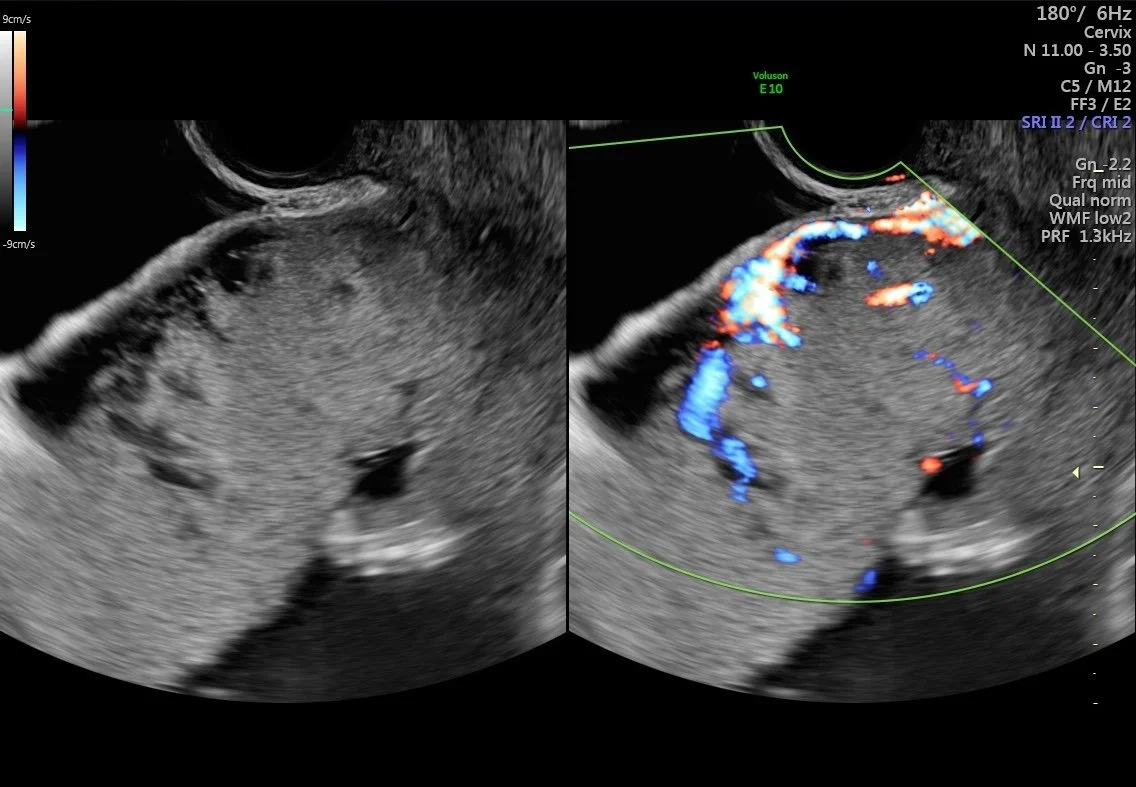

Potential Placenta Accreta

A placenta previa paired with suspected accreta was identified and tracked throughout this pregnancy. With a previous history of two cesarean sections along with a suspected accreta and previa, a third cesarean was scheduled for 34 weeks. The delivery plan would also involve an immediate hysterectomy given these indications.

When the patient delivered, everyone was surprised to discover no accreta, although placenta previa was still present. The patient and baby were both healthy, and the hysterectomy was not performed.